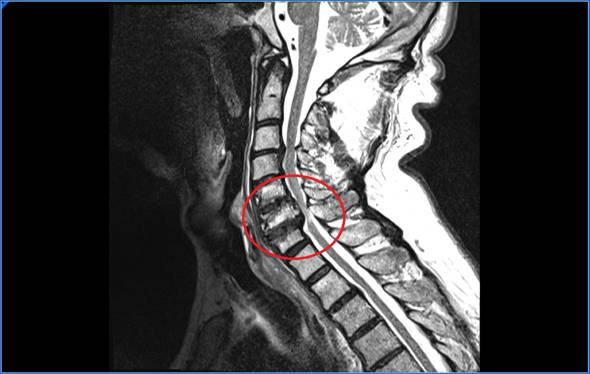

Resonancia Magnética. Es la principal prueba de la que disponemos, con una resonancia podremos ver el grado de compresión, medir el área de la médula, el diámetro del canal cervical. Hay ocasiones en los que en la resonancia la médula aparece más brillante cuando esto ocurre el diagnóstico de mielopatía cervical es más fácil.

Imágenes de resonancia

Como hemos comentado en ocasiones la médula aparece con zonas más brillante cuando está comprometida. Que aparezcan estas imágenes esta relacionado con una mayor compresión pero no con el tiempo de evolución.